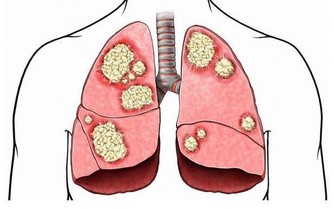

冬季可以說是前列腺炎的最高發季節,主要就是指前列腺受涼而引起,

要知道的是,受涼對前列腺的影響非常大,可以直接的影響到前列腺的功能,

所以,冬季預防前列腺炎,最關鍵的就是避免受涼,注意保暖。下面就冬季前列腺炎的預防方式進行介紹: